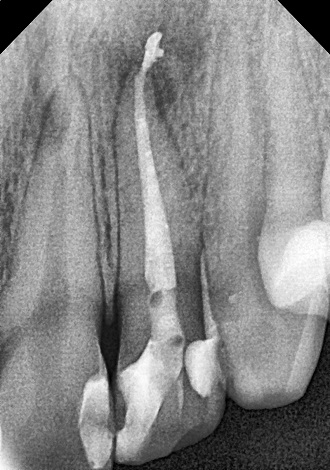

Лікування запалення нерва в зубі полягає в ретельному видаленні залишків нерва з зуба, очищення кореневого каналу і подальшому його пломбування.

5. визначити глибину каналів зубного кореня;

6. механічна розробка каналів;

7. хімічна обробка каналів;

8. герметична обтурація.

Якісно запломбовані кореневі канали є основою довговічності. Тому очищення і пломбування кореневих каналів в «Домі Стоматології» приділяється особлива увага! Після пломбування кореневих каналів проводиться контроль якості пломбування за допомогою знімка.